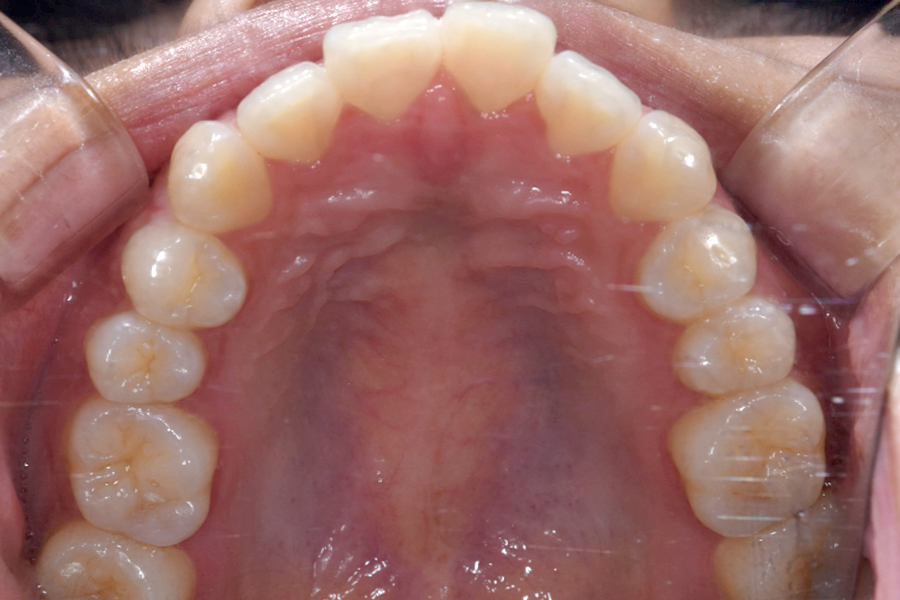

治療後

主訴 上下前歯のすきっ歯が気になる

期間 1年5か月

費用 マウスピース矯正

956,596円(税込)

治療内容 目立ちにくいマウスピース矯正(非抜歯矯正)

歯と歯の間に隙間をつくることにより、歯列弓を広げながら治療を行いました。

治療に伴うリスク ・後戻りする可能性があるのでリテーナーを最低でも矯正期間以上はつけること。

・稀にほっぺた、唇、舌などに口内炎や傷ができることがあります。